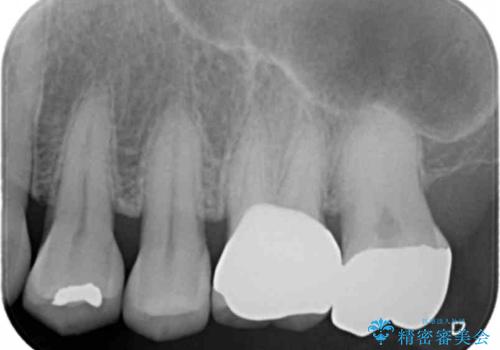

- 他院で装着した被せ物が割れたとのことで来院されました。

被せ物の厚みが確保されていなかったため、向かいの歯とのスペースを確保するように修正していきます。

被せ物の厚みが十分に確保できていないと、材料によっては今回のように割れてしまうことがあります。

被せ物の材料を変えるか、厚みを確保することでそのリスクを抑えることができます。

今回はセラミックでの再治療をご希望されたため被せ物の厚みを確保することで対応しました。

- 左上6/仮歯+ジルコニアクラウン:11,000円+110,000円費用は治療当時の料金となります